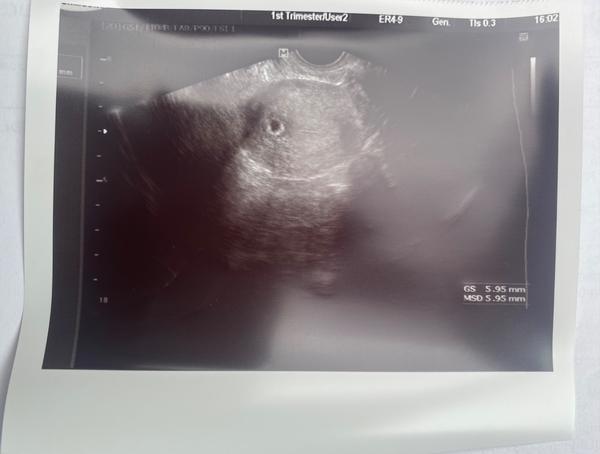

@esmee3 krásna bublinka 😍

@zuzsat no napísala tam zatiaľ podľa ms, 6+4, potom sa to upraví keď bude vidieť embryjko. Lebo reálne asi 5+2